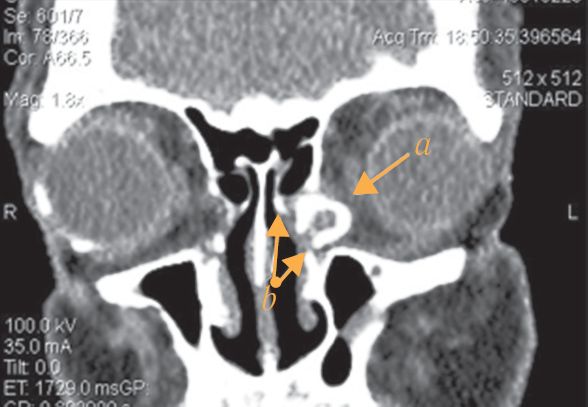

All patients underwent endonasal balloon dacryoplasty using a 6-mm balloon (Acclarent Inc., USA; Fig. 1). The length of the working part of the balloon was 16 mm and diameter 2.2 mm, and after inflation, it was 6 mm. A luer lock fastening was in place in the proximal part of the balloon for connection to the indeflator.

Fig. 1. Photo of a balloon catheter of 6 mm diameter in inflated state (Acclaren Inc., USA): a – active part of the balloon catheter; b – Luer-lock for connection with the indeflator

Рис. 1. Внешний вид баллонного катетера диаметром 6 мм в раздутом состоянии (Acclarent Inc., США): a — активная часть баллонного катетера; b — крепление типа Luer-lock для соединения с индефлятором